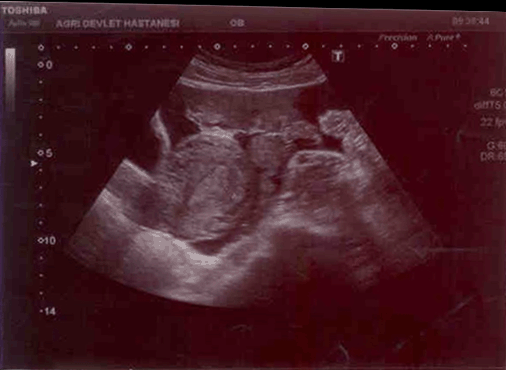

A 21-year-old female admitted into emergency room of Agri Obstetrics and Gynecology Hospital with syncope, nausea, emesis and vaginal hemorrhaging in staining character. She was not having her period for 2 months and was diagnosed with anembryonic pregnancy in another private medical clinic. Eight hours before admission, the patient was treated with dilatation and curettage (D&C) under elective conditions in the same medical clinic she was diagnosed without any complications and the patient was discharged after the operation. Postoperatively 8 hours, the patient gradually started to feel unwell and finally was brought to the emergency room of our hospital. The medical history stated that this was her first pregnancy and she had no history of a coexisting illness or medication. Following admission, no active hemorrhage was diagnosed during speculum inspection but routine hemorrhage in staining character was common following such procedures. Abdominal examination showed a widely distributed tenderness in all quadrants during palpation and rebound finding was prominent in lower quadrants. Dyspnea and palpitations were seen in supine position. Ultrasonography (USG) examination showed a normal uterus, endometrium thickness (10 mm) and normal bilateral ovary structures. Disseminated dense fluid retention in a hemorrhagic fashion was detected in Douglas and paraovarian areas in addition to intestinal segments. The image was consistent with an embryo in yolk sac with a gestational age of 6 weeks and six days in ampullar portion of right fallopian tube. (Figure 1) and (Figure 2). The patient vital signs were blood pressure 80/40 mmHg, pulse 98/minute and hemoglobin was 7.8 g/dl, HTC 22, Platelet count 182000 and WBC 14000. Patient was closely followed and the USG images taken before D&C procedure were obtained from the patient. The images revealed a gestational sac consistent with an anembryonic pregnancy measuring 33 mm located in uterine fundus and the procedure was actually a D&C for abortion (Figure 3) and (Figure 4). Patient's relatives were notified of the medical situation of the patient and our initial diagnoses were either a uterine rupture or a coexisting pregnancy of a heterotopic type. Laparotomy was planned after assessment of the clinical situation of the patient and risks and details of the procedure was shared with the patient. After obtaining 3 units of erythrocyte suspension, the abdominal access was done using a Pfannenstiel incision. Dense disseminated fluid was detected and about 2 liters. of this hemorrhagic fluid was aspirated. After aspiration, no signs of perforation was found on the front or rear surface of the uterus. In tubal structures inspection, left tube and ovary was normal but right tube had an actively bleeding gestational sac about 2 cm in diameter on ampullary portion and a full thickness perforated tubular structure confirmed our diagnosis of heterotopic pregnancy (Figure 5). Salpingostomy was chosen after considering patient's age and gravidity. The tube was repaired using 3–0 Prolene sutures after removal of all trophoblastic structures. Operation was finished after checking for hemorrhage and an abdominal drainage tube was inserted for follow-up. Three units erythrocyte suspension was used during the operation. Within 48 hours in postoperative period, 50 cm3 serohemorrhagic fluid was collected in the drain. The abdominal drainage tube was removed on the third day of operation and patient was discharged from the hospital with full recovery. The patient was advised to go to regular follow-up in gynecology and obstetrics clinic. b-hCG values dropped below 5 and no complications were seen in incisional scar area. She was also informed about the possible risks that might occur in future pregnancies.

Figure 1: Ectopic pregnancy discerned in right tubal structures.